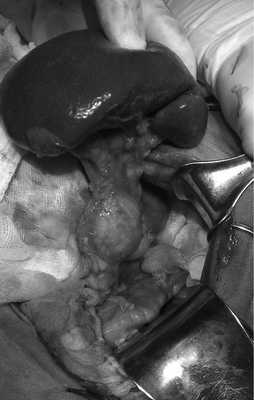

После предоперационной подготовки 13.10 больной оперирован. После лапаротомии подтверждена инвагинация правых отделов толстой кишки в поперечную ободочную кишку. Инвагинированные кишки расправлены. В куполе слепой кишки обнаружено подвижное мягкоэластической консистенции объемное образование до 7 см в диаметре. Выполнена правосторонняя гемиколэктомия с наложением илеотрансверзоанастомоза конец в бок с помощью сшивающего аппарата.

Макропрепарат: отрезок кишки длиной 20 см, образование исходит из тканей в области баугиниевой заслонки, экзофитное, грушевидной формы, с изъязвлениями, размером 7×4×4 см, суживает просвет кишки до точечного. На разрезе — жировая ткань (рис. 2). При гистологическом исследовании картина липомы толстой кишки.

Рис. 2. Макропрепарат.